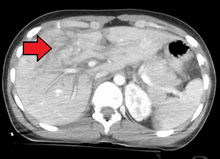

Grade 4 liver laceration

Imaging, such as the use of ultrasound or a computed tomography scan, is the generally preferred way of diagnosis as it is more accurate and is sensitive to bleeding, however; due to logistics this is not always possible.[4] For a person who is hemodynamically unstable a focused assessment with sonography for trauma (FAST) scan may take place which is used to find free floating fluid in the right upper quadrant and left lower quadrant of the abdomen. A physical examination may be used but is typically inaccurate in blunt trauma, unlike in penetrating trauma where the trajectory the projectile took can be followed digitally.[5] A diagnostic peritoneal lavage (DPL) may also be utilized but has limited application as it is hard to determine the origin of the bleeding.[6]